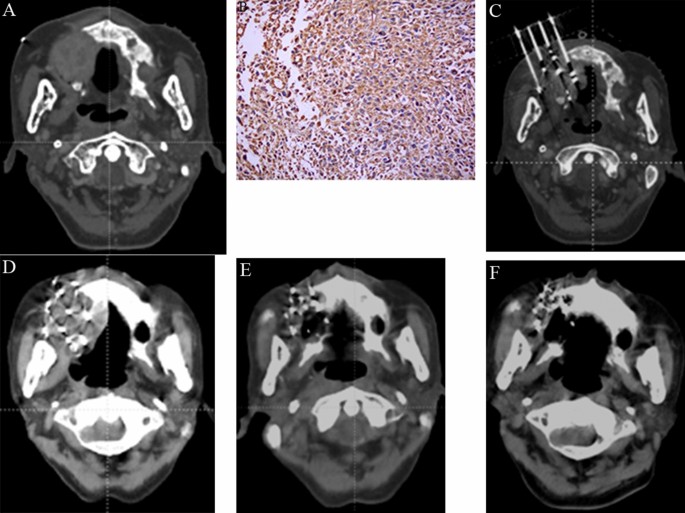

*Evaluation of the efficacy of CT-guided 3D template-assisted 125I *

The Rise of Supply Chain Management adioactive materials are implanted into the tissues to be treated. and related matters.. Getting Internal Radiation Therapy (Brachytherapy). Meaningless in Internal radiation is also called brachytherapy. A radioactive implant is put inside the body in or near the tumor., Evaluation of the efficacy of CT-guided 3D template-assisted 125I , Evaluation of the efficacy of CT-guided 3D template-assisted 125I